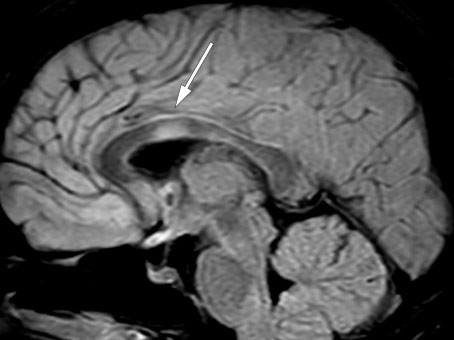

MRI of the brain and total medulla showed enhancement in more than 50 % of the medulla diameter with weak contrast enhancement at levels C4–C5, C6–C7 and Th11–Th12 (Figure 1), but improvement in the lesions that had previously suggested meningitis. The radiologist considered the images to be most consistent with acute disseminated encephalomyelitis. A new lumbar puncture (Table 1) showed an increasing cell count and moderately increased total protein and albumin consistent with blood-brain barrier failure. On the basis of the increasing cell count in the cerebrospinal fluid, aciclovir was again administered until the PCR result for herpes simplex virus came back negative.

Figure 1 Sagittal T2-weighted MRI showed lesions consistent with myelitis at multiple levels.